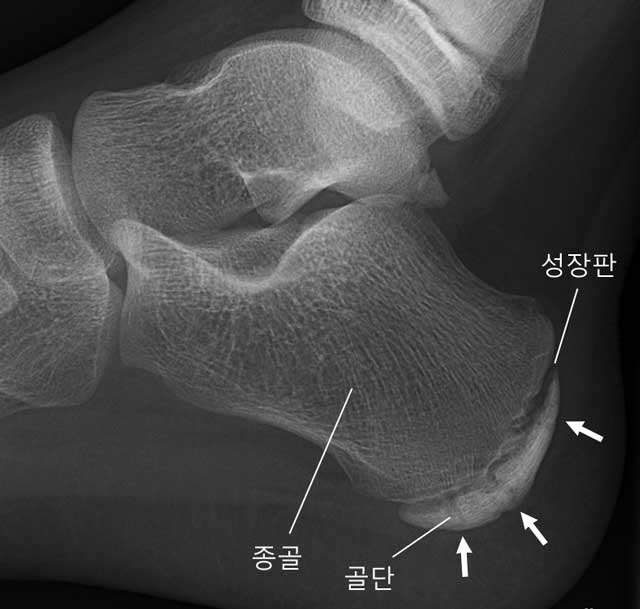

종골 골단염 (세버병. Sever's Disease)

성장기에는 종골 골단에 성장판이 있어 충격에 약하기 때문에 성장기 어린이에게 보다 자주 발생할 수 있고, 주로 8~15세에 발병이 많은 편이며, 여자보다는 남자에게 더 자주 발생합니다.